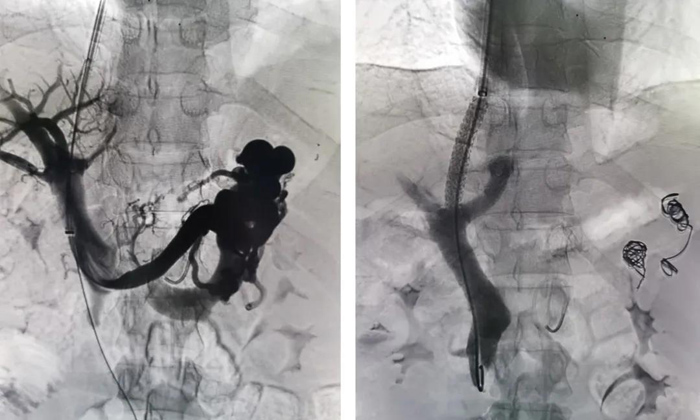

手術如期進行,李強主治醫師施行此次手術。術中由頸靜脈處穿刺插管至肝靜脈,在肝實質內穿刺門靜脈,并植入支架,建立門靜脈與肝靜脈之間的通道;手術同時栓塞曲張靜脈,從而降低門靜脈壓力,減輕食管胃底靜脈曲張程度及出血風險。最終手術順利完成,患者和家屬臉上也露出了滿意的微笑。